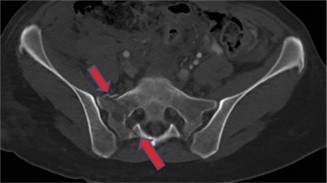

A 24-year-old male presents following a motor vehicle collision. His primary complaint is of lower back pain.…